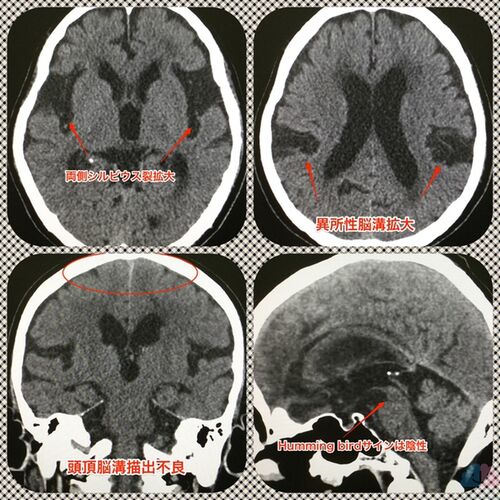

【症例報告】PSP+iNPHの方。

今回は、PSP(進行性核上性麻痺)+iNPH(特発性正常圧水頭症)を合併していたNMさんをご紹介する。 前医の脳神経外科でPSPを指摘され、グルタチオン点滴が開始されていたが、効果は感じていなかった。 当院で初回1600mgでグルタチオン点滴を行ったところ即座に歩行に…